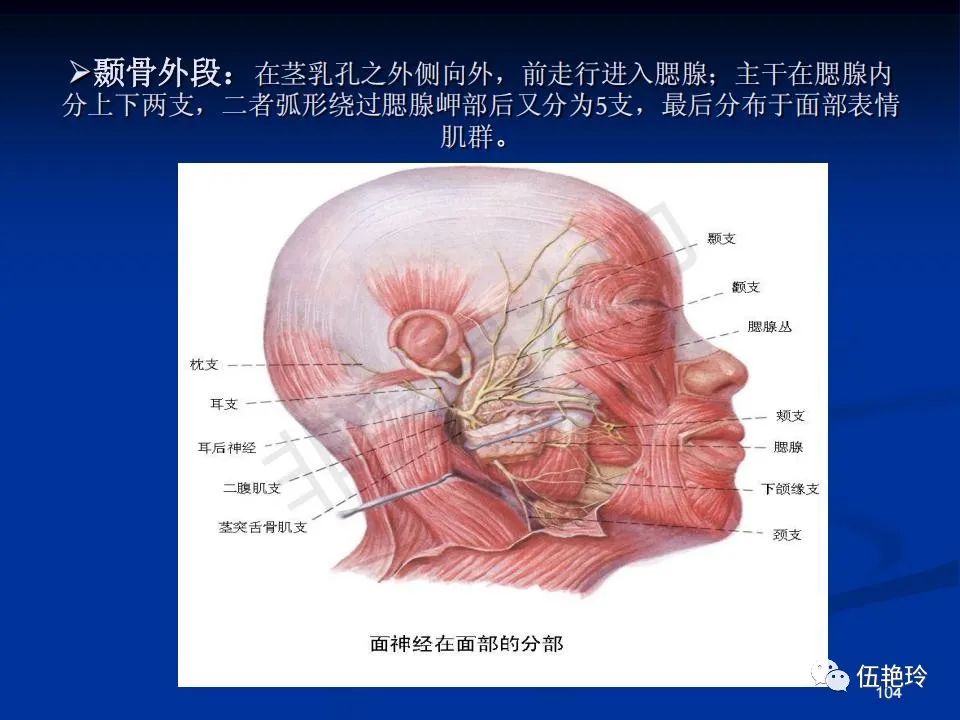

耳与面神经的解剖